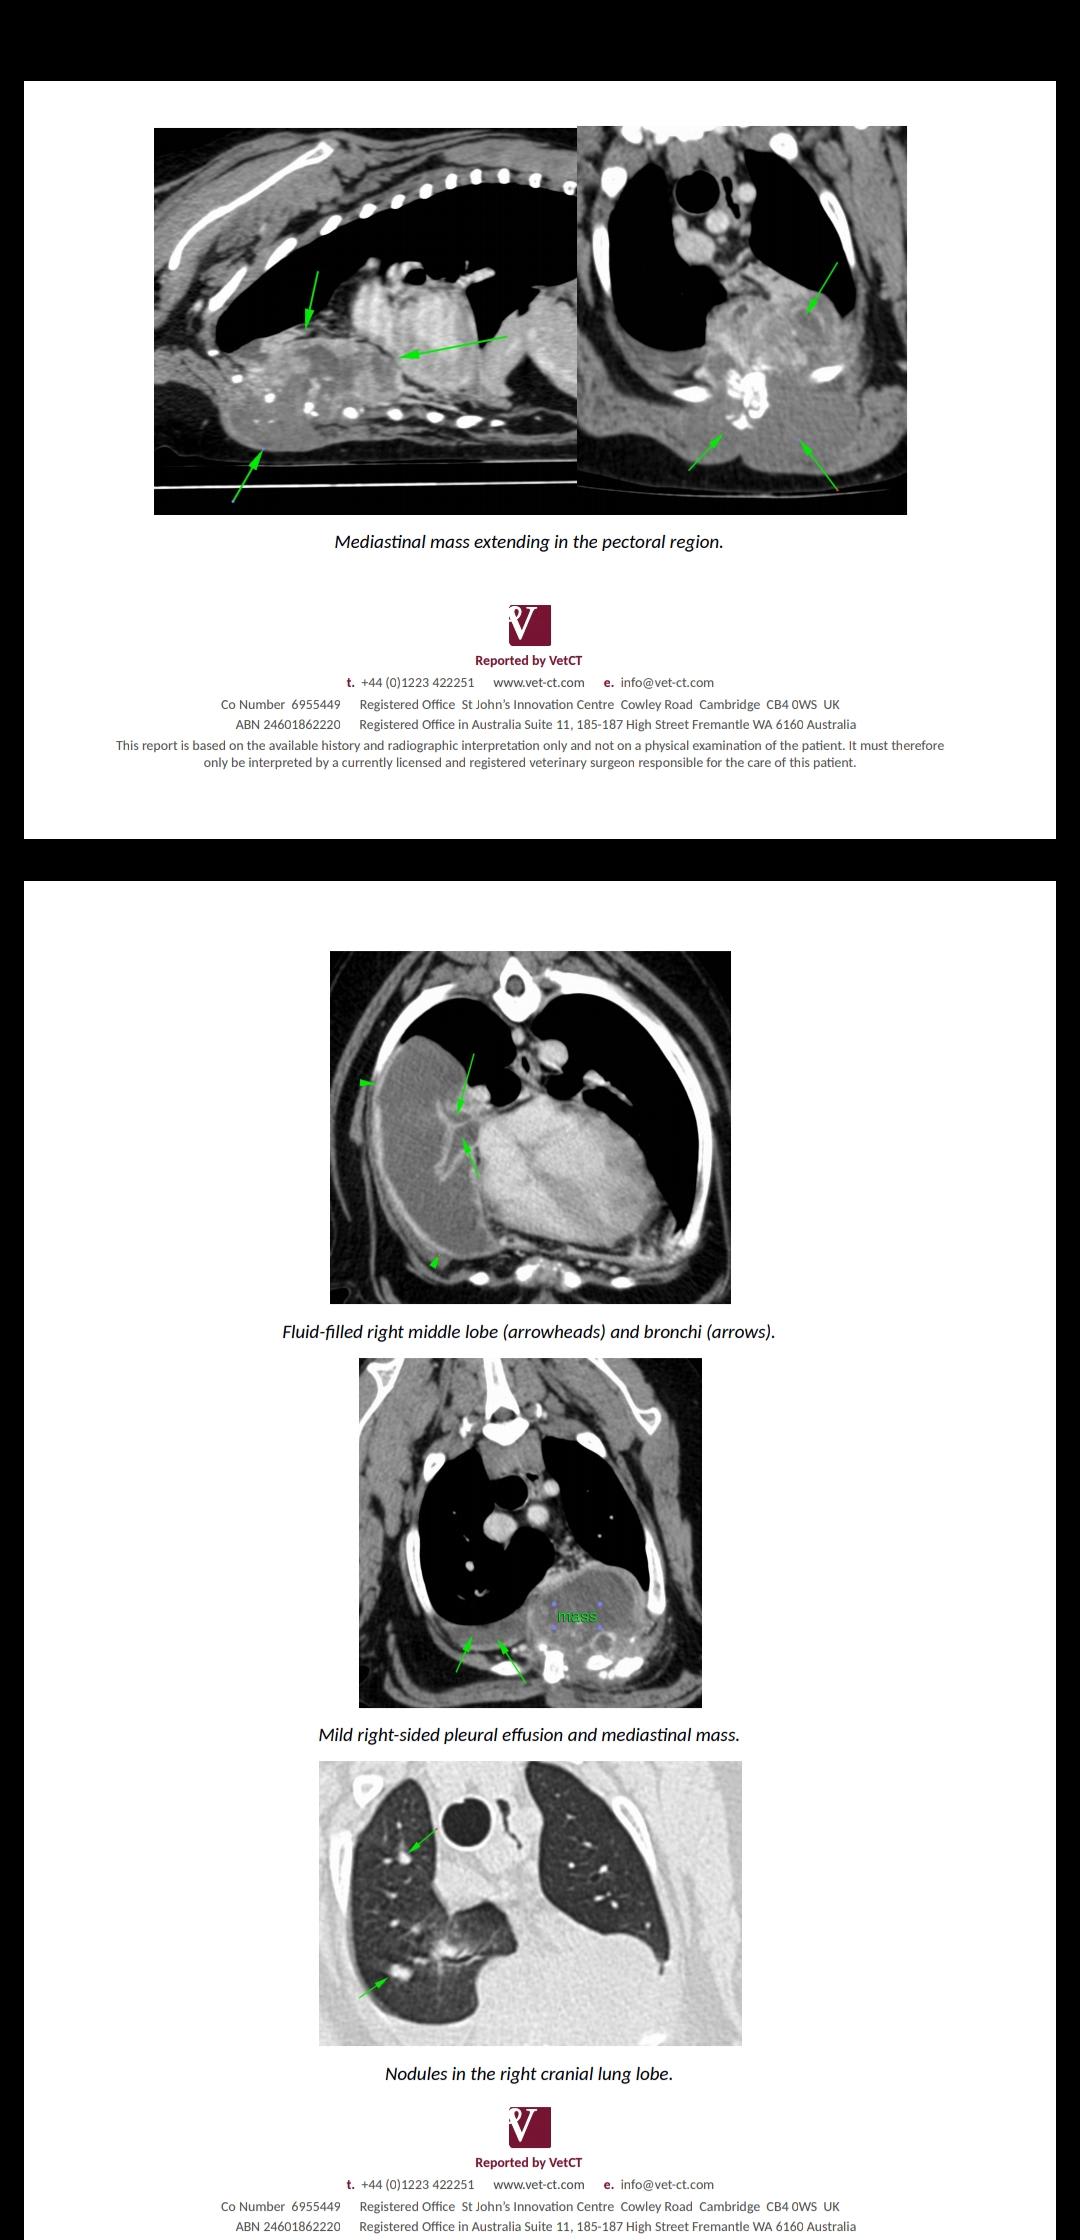

I would appreciate an opinion as our vet is getting very frustrating. CT scan shows a mass in our elderly dog who presented with anaemia. Any ideas? We have been waiting weeks for answers now. Is it worth putting him through anymore procedures that stress him out? Apparently the biopsy they took of the mass doesn't tell them what it is. Thank you

HI, thanks for using Petco Pet Education Center, formerly Petcoach! Poor Yogi! I am sorry you are going through this. It is hard to jump in to a case like this with only a CT image. It might be better for you to sign up for a consult with one of out Vets to have a one on one text conversation. My impression of the CT is that there is a mass in Yogi's chest, in the mediastinum. There is abnormal fluid accumulation likely from the mass and there are also suspicious nodules with in his lung tissue. Which I think is safe to assume is metastatic. If Yogi was my dog and he had a chest tumor with suspected metastatic disease I wouldn't pursue further diagnosistics or surgery as his prognosis is very poor. To put him through a painful surgery when it has spread seems unfair for him. If the "biopsy" was really an aspirate they tend to sometimes be non-diagnostic as most tumor cells do not exfoliate well in to a needle. A true tissue sample would be needed. I am not sure knowing which type of cancer he has will change how I would proceed. Another option is to see a Veterinary Specialist. I would recommend an Oncologist. Sitting down with all the tests and having a discussion may help you. You can also call your Vet and ask to sit and talk about the results with out Yogi present. Just so you know all that you can before making any decisions. I am again very sorry for you and Yogi. Let me know if I can help in any other way.